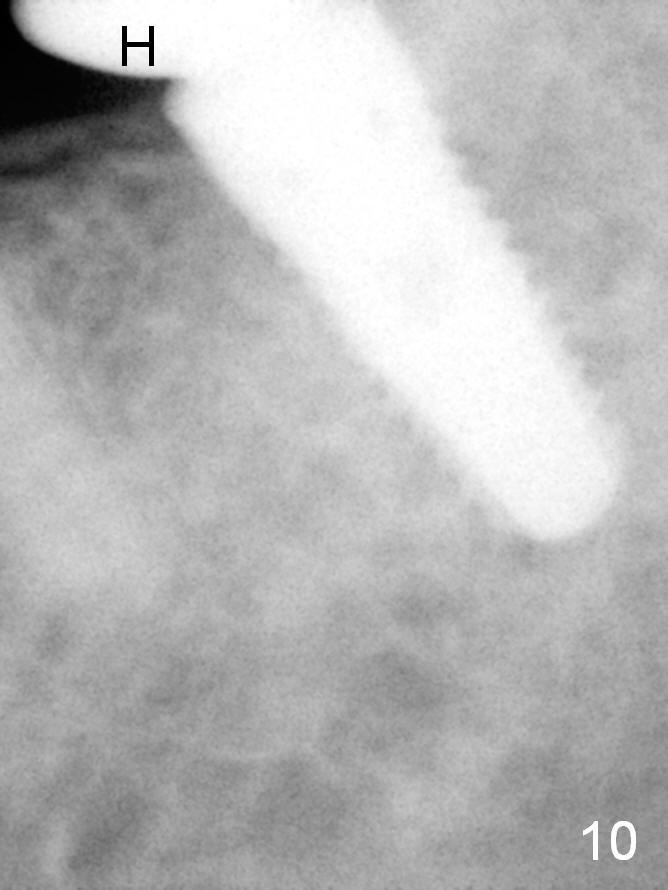

A 48-year-old lady is a dental phobic, requesting extraction of the lower left 2nd molar (Fig.1).   She returns for implant placement 9 months post extraction (Fig.2).  The ridge is mildly to moderately atrophic.  It appears that a 5x12 mm implant is appropriate for the site (Fig.3).  For safety, osteotomy is initiated at the depth of 10 mm; it appears that there is enough height for a 12 mm implant (Fig.4).  The depth is controlled by drill stopper (Fig.5 S).  Finally a 5x12 mm implant is apparently safely placed (Fig.6).  A healing abutment is placed and the incision is sutured with 4-0 Chromic gut (Fig.7).  Perio dressing is applied around the healing abutment for wound protection (Fig.8).  It appears that the healing abutment (Fig.8': *) helps stabilize the perio dressing, which remains in place 1 week postop.  When the perio dressing is removed, the wound around the healing abutment is healing (Fig.9).  There is no bone loss around the implant 3 months postop (Fig.10 (H: healing abutment), or 16 months postop (i.e., 9 months post cementation, Fig.11,12).  The patient complains of pain when she chews with the implant crown, but pain stops whenever she does not bite.  Percussion does not elicit any discomfort.  The gingiva is healthy.  There is possibility of the buccal plate being thin or the lingual plate being perforated in the submandibular fossa.  If the discomfort remains the same next 6 months, CBCT will be prescribed.